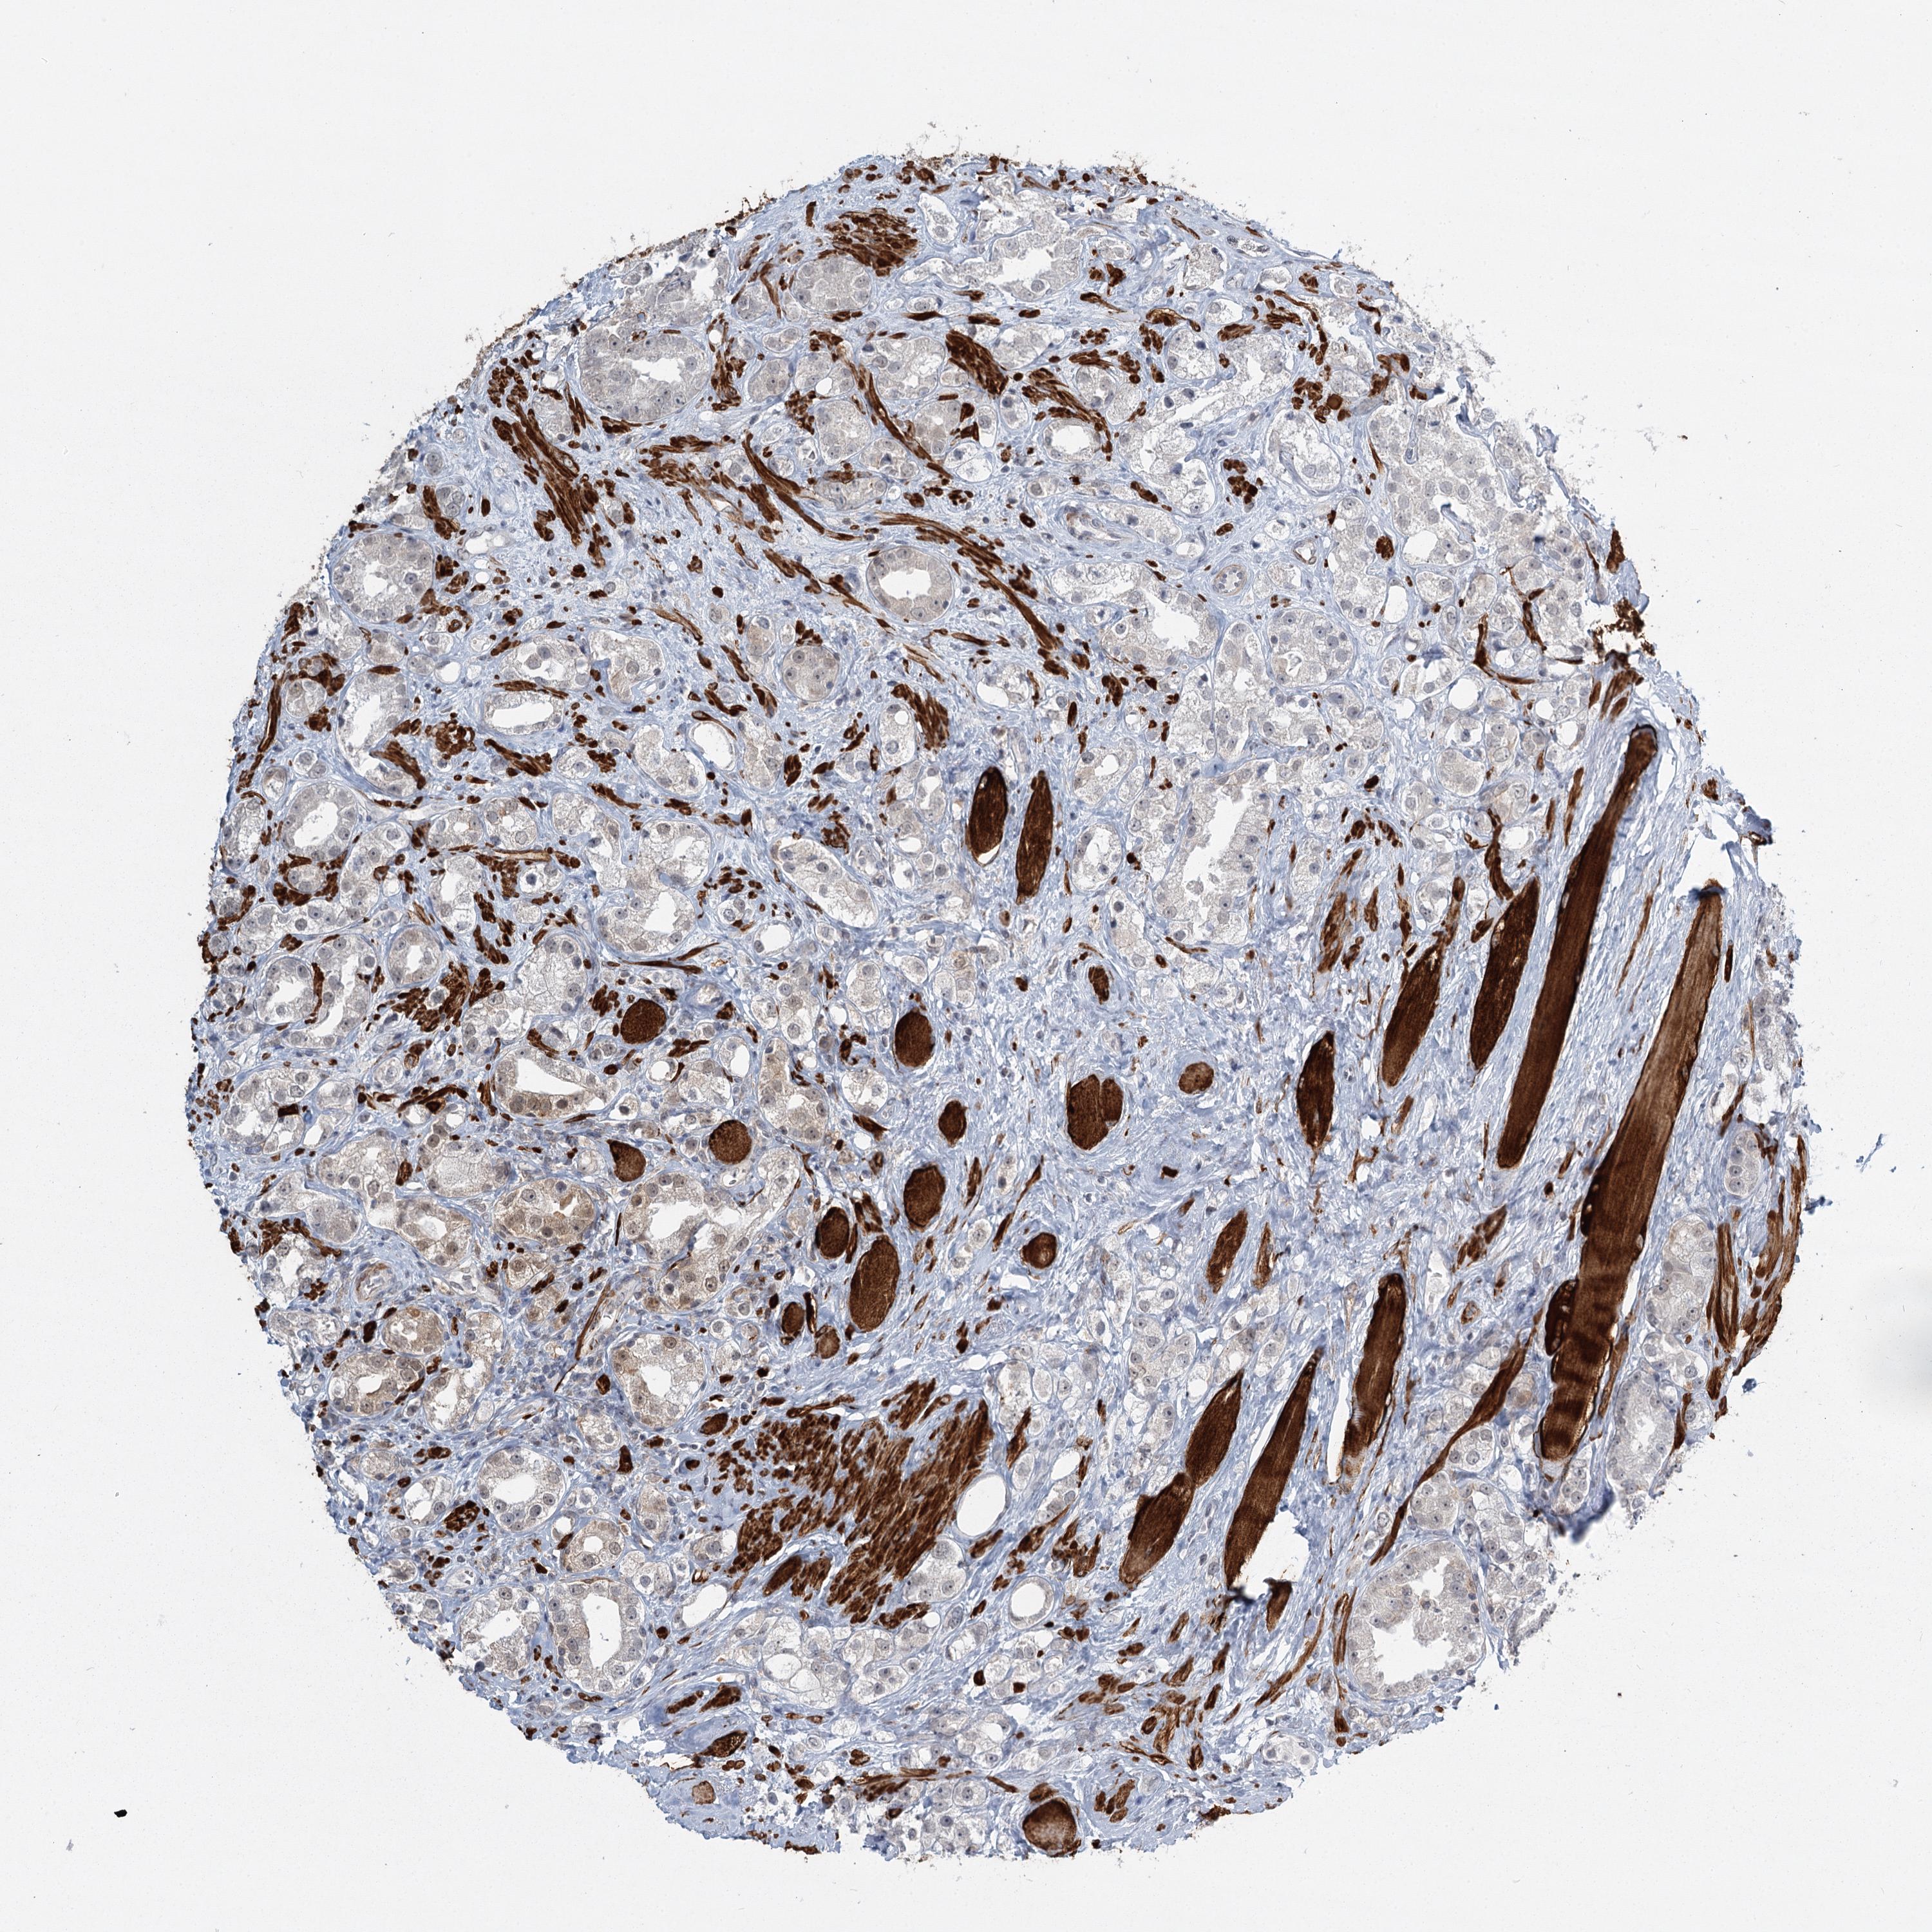

PROSTATE CANCER - Protein expressioni

A mouse-over function shows sample information and annotation data. Click on an image to view it in a full screen mode. Samples can be filtered based on level of antibody staining by selecting one or several of the following categories: high, medium, low and not detected. The assay and annotation is described here.

Note that samples used for immunohistochemistry by the Human Protein Atlas do not correspond to samples in the TCGA dataset.

Antibody stainingi

Antibody staining in the annotated cell types in the current human tissue is reported as not detected, low, medium, or high, based on conventional immunohistochemistry profiling in selected tissues. This score is based on the combination of the staining intensity and fraction of stained cells.

Each image is clickable and will lead to virtual microscopy that enables deeper exploration of all samples and also displays staining intensity scores, fraction scores and subcellular localization as well as patient and tissue information for each sample.

Antibody HPA023187

Antibody CAB034226

Staining

High

Medium

Low

Not detected

Intensity

Strong

Moderate

Weak

Negative

Quantity

>75%

75%-25%

<25%

None

Location

Nuclear

Cytoplasmic/membranous

Cytoplasmic/membranous,nuclear

Adenocarcinoma, High grade

Adenocarcinoma, Low grade

Adenocarcinoma, NOS